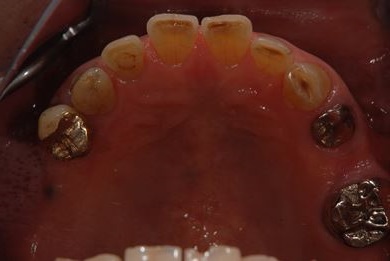

抜歯即日スピードインプラント治療+歯周外科治療

| 性別/年齢 | 男性 / 62歳 | ||||||||||||||||||||||||||||||||

| 主訴 | 左下の奥歯のブリッジがゆれて、痛みがある。 | ||||||||||||||||||||||||||||||||

| 治療方針 | 抜歯と同時にインプラント埋入を行い、治療期間を短縮する。 | ||||||||||||||||||||||||||||||||

| 治療内容 | インプラント2本(抜歯即日スピードインプラント)、ハイブリッドセラミッククラウン2本、歯周外科治療 | ||||||||||||||||||||||||||||||||